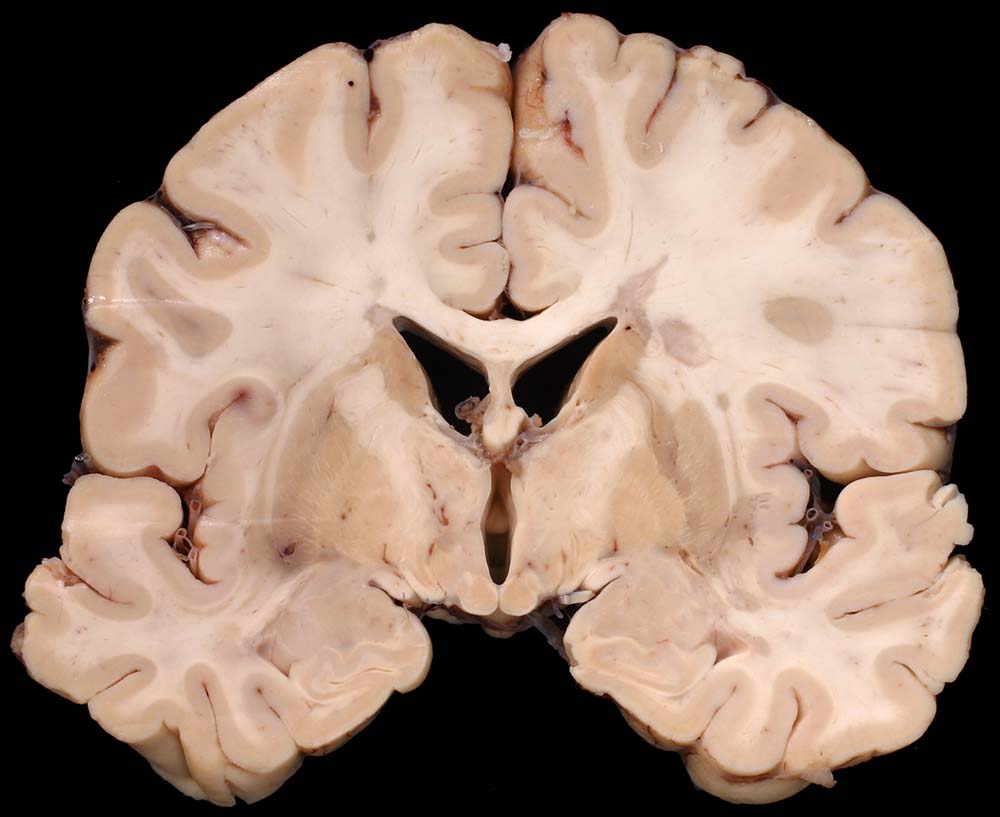

PathoPic ID 8793 - Periventrikulär betonte Entmarkungsherde bei multipler Sklerose

Periventrikulär betonte Entmarkungsherde bei multipler Sklerose

Systemerkrankung/Immunpathologie

Hirn parietal

Nervensystem

Periventrikulär betonte irregulär begrenzte

Grauverfärbung des Marklagers.

Multiple Sklerose (Erstdiagnose vor 30 Jahren) mit spastischer Paraparese und neurogener Blasenmotorikstörung.

Makroskopie